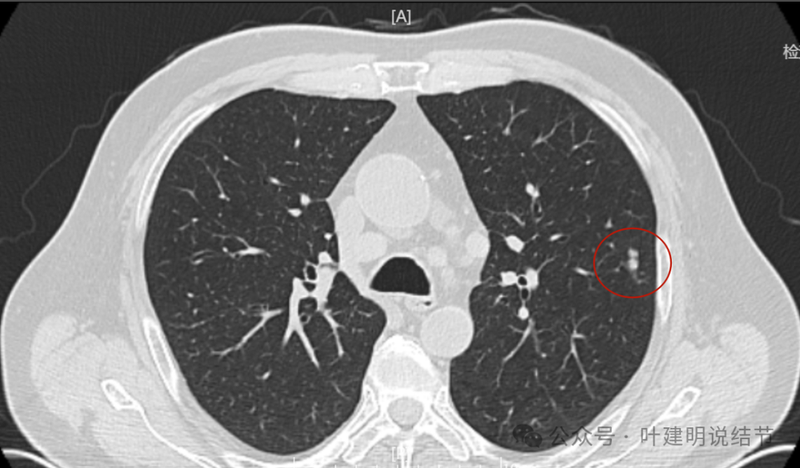

2024年1月病灶较3个月前明显增大进展,是实性小结节,有微小血管走向病灶。

2024年5月病灶又有增大进展,实性密度,轮廓较清。